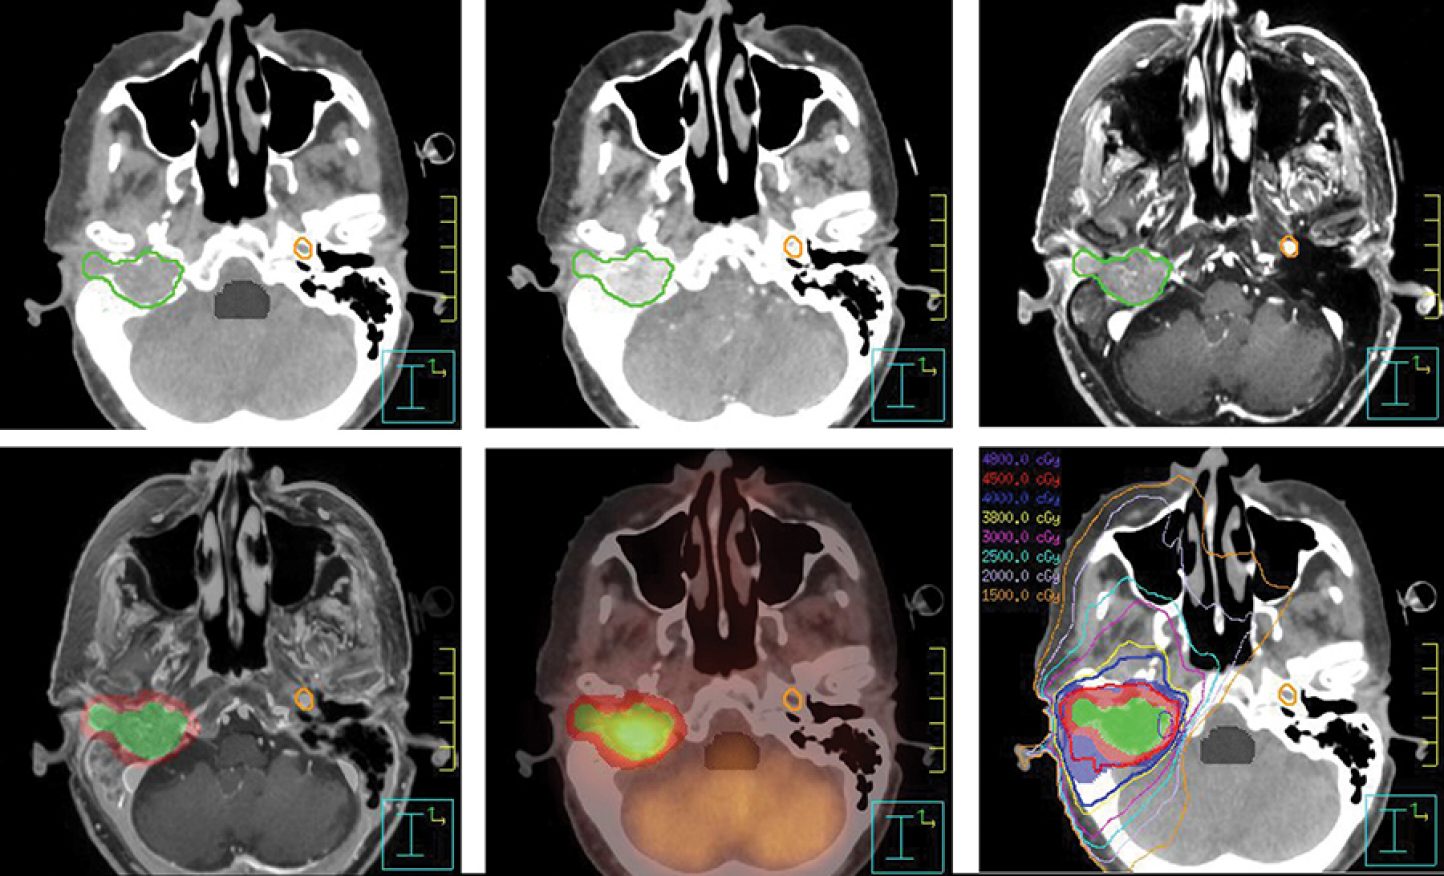

Cáncer de cara recurrente

Fuente de la imagen de portada: MD Anderson Cancer Center.